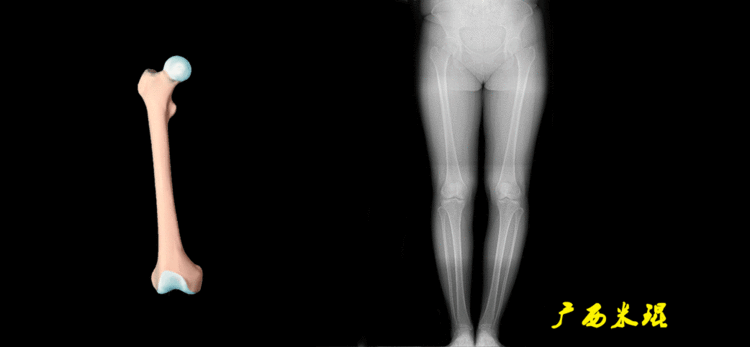

下肢力线及相关角度测量的前提是必须拍摄标准的站立位也就是负重位的下肢全长片。目前这样的照片都是放射科的技师在电脑上拼接出来的,大部分医院的DR都能够做到这一点。

患者直立于摄影架上,后背贴近摄影架,双手自然下垂,膝关节尽量伸直,足部与双肩同宽,要求投照时双髌骨朝正前方,通常患者双足尖应平行向前即可。

提醒一下大家,拍摄过程中应避免下肢的外旋和内旋。如果有一侧肢体短缩时,投照应当用脚垫垫高短缩肢体,使骨盆保持水平,这样下肢短缩测量才精确。如果有肢体旋转畸形时,还是以髌骨朝前为标准,虽然此时双足可能不能保持平行。

二、下肢全长片的基本要求

无论如何,拍摄出来的下肢全长片必须包含髋关节中心、膝关节中心及踝关节中心,否则对临床是无用的。有了一张下肢的全长照片,我们需要确定下肢关节的中心点,通过中心点画出下肢的各种轴线,然后利用轴线与关节线的相交得出各种所需要的角度。